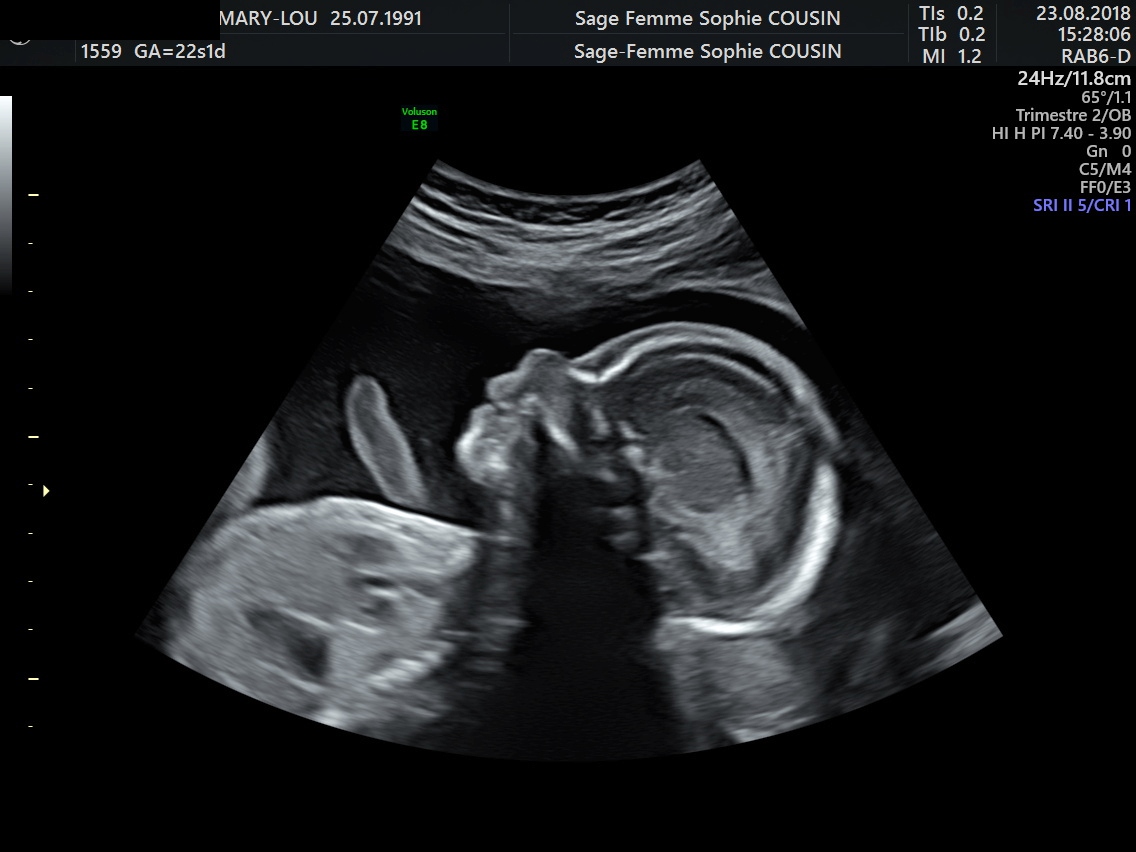

2-Echographie de 22sa

C'est une échographie très importante.

Elle a pour but de vérifier les organes du fœtus, l'absence de malformation , sa croissance, la position du placenta, le sexe du fœtus, la vitalité fœtale, la quantité de liquide amniotique.